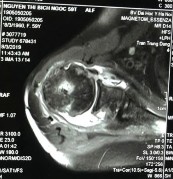

Hình phụ lục 2A: Phim CHT bệnh nhân trước mổ cho thấy rách lớn và co rút gân trên và dưới gai trên phim cắt mặt phẳng trán.

(Nguồn: BN nghiên cứu)